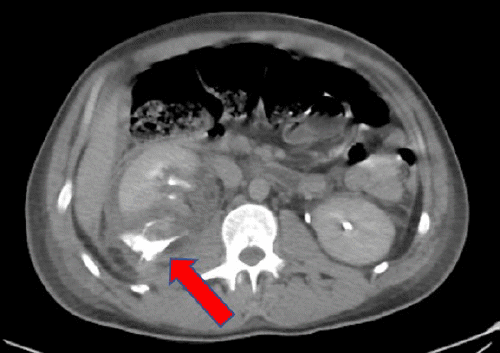

A 31-year-old male trauma transfer from another hospital sustained blunt abdominal trauma following a snowboarding accident. The referring hospital's CT scan revealed a liver laceration (grade IV), extensive right kidney injury (grade IV) with a perinephric hematoma, possible damage to the right renal collecting system with extravasation of urine, and a fractured 10th right rib (Figure 1).

Figure 1. Preoperative Imaging Findings. Published with Permission

B) Grade IV right kidney injury with perinephric hematoma and possible injury to the proximal ureter (arrow), evident on delayed films.